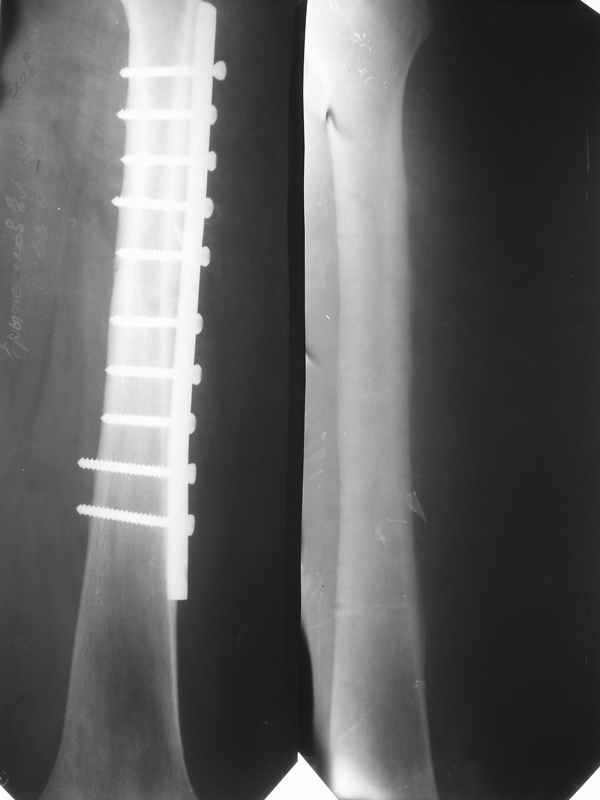

Здравствуйте. К нам поступил мальчик 15 лет с застарелым 7-месячным вывихом бедра из области. Травма мотоциклетная, при поступлении в больницу по месту жительства диагностирован перелом диафиза бедра и не распознан вывих бедра с этой же стороны.

Бедро было синтезировано пластиной и успешно срослось. Как поступить сейчас с вывихом? По КТ видны интерпонированные отломки, впечатление что это фрагменты головки бедра. Поделитесь, пожалуста, опытом. Спасибо.

Уважаемые коллеги! Две недели назади мы прооперировали данного пациента: монтаж аппарата таз-бедро (с двусторонней фиксацией за крылья) и постепенная дистракция. Достигнуто низведение бедра.

планируется открытое вправление вывиха с удалением интерпонированных тканей.